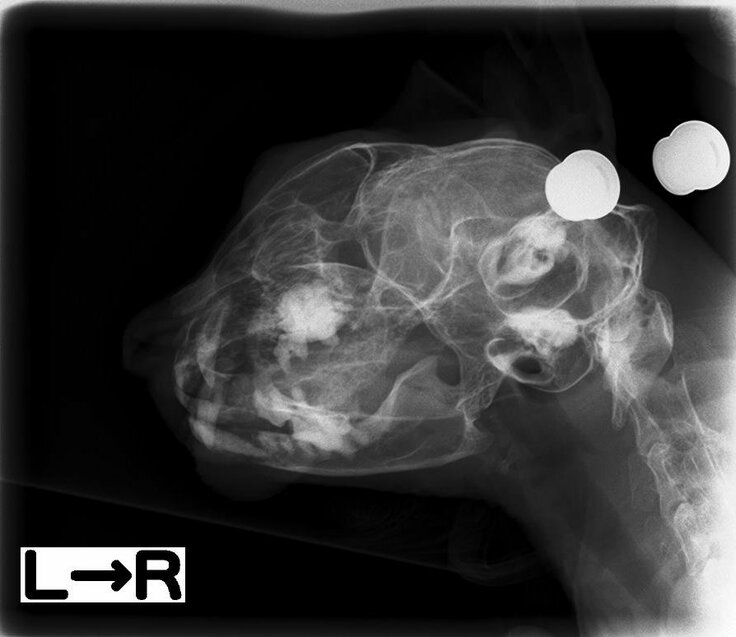

大量出血 レントゲン

それなら骨はまだ大丈夫なのか気になり、レントゲンを撮ってもらうことにしました。

左顎は正常 顎の骨のふちが白くくっきり見えます。

右顎は途中でモヤモヤっとして前後をがん細胞がつないでいるらしい

人間なら虫歯が神経に当たるだけで狂いそうに痛い。

よくこれだけ骨が溶けてもがまんしたと思います。

顎の下はカチカチになっており、触っても痛がりません。

まだ一気に顎がなくなるってことはないという話でした。